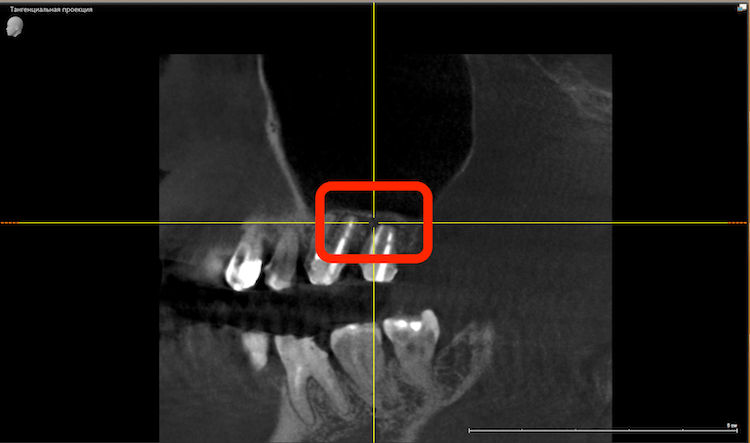

КТ-диагностика

На КТ снимке обнаружили кистогранулемы, которые являлись источником боли пациента. Также, на нижней челюсти выявили пародонтит второй степени.